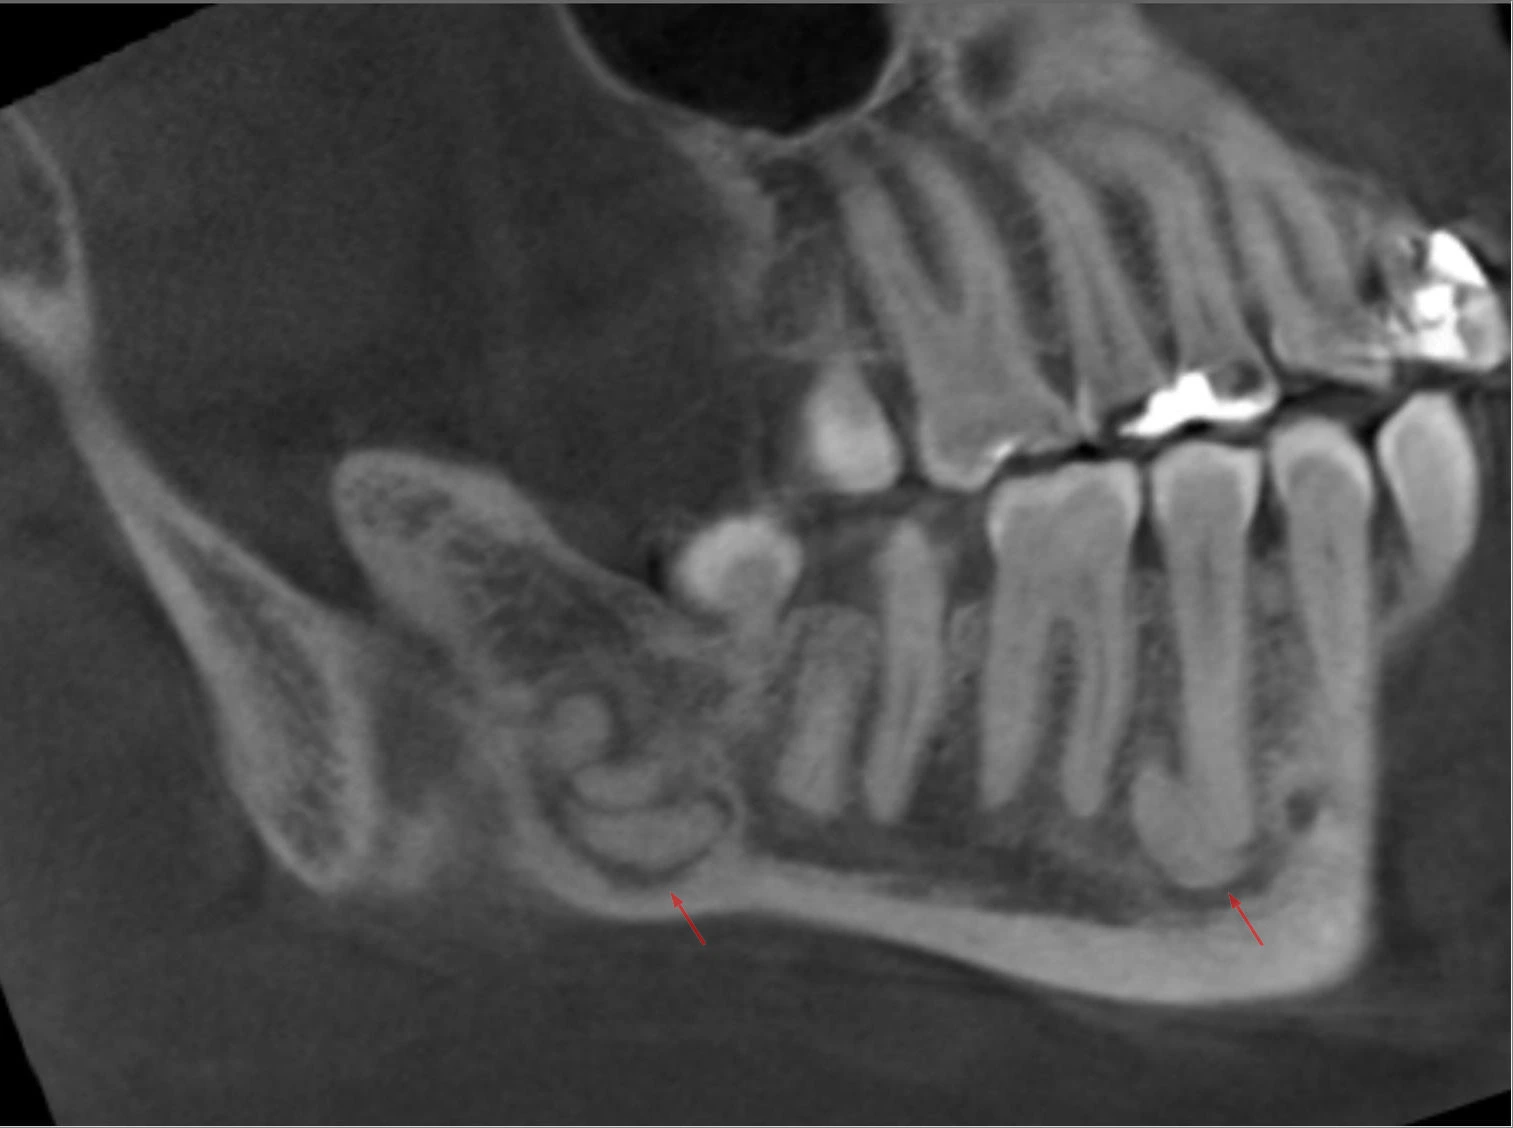

• Complex composite odontoma : Consists of non-discrete, irregular masses of calcified dental tissues that have no morphologic similarity even to rudimentary teeth.

• Often seen as radiopaque mass, situated between the roots of teeth or associated with unerupted teeth.

• Complex odontomas : Irregular mass of calcified material surrounded by a narrow radiolucent band with a smooth outer periphery.

• Deutsch: Odontom(e) im Unterkiefer bei einer Mittvierzigerin: Dichte, amorphe Formation in der Nähe aber nicht ausgehend von den Zahnwurzeln. Befund nicht histologisch bestätigt, aber gut passend. DVT in verschiedenen Reformatierungen.